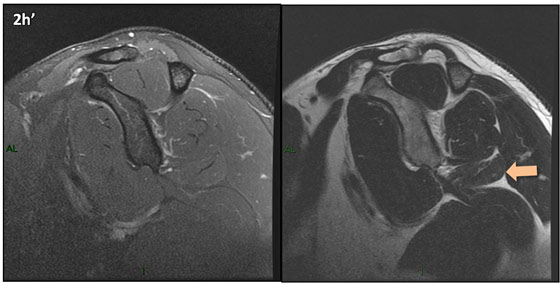

Figura 2 (a-j)': Imagens consecutivas de RM no plano sagital nas ponderaçõesT2 com supressão de gordura (DP SG) à esquerda e T2 à direita. Clique na seta para passar as imagens.

Figura 2a’ mostrando os tendões do subescapular (seta rosa), da cabeça longa do bíceps (seta verde), do supraespinhal (seta vermelha), do infraespinhal (seta laranja) e do redondo menor (seta amarela).

Figuras 2b a 2j’: Acompanhando o tendão do redondo menor (seta amarela fina) é possível notar lipossubstituição ao redor da junção miotendínea (setas amarelas grossas) e a atrofia principalmente da porção mais lateral (seta salmão). A porção mais medial (seta branca) tem volume preservado.

Repare que estas alterações também não são evidentes nas imagens com supressão de gordura no plano sagital.